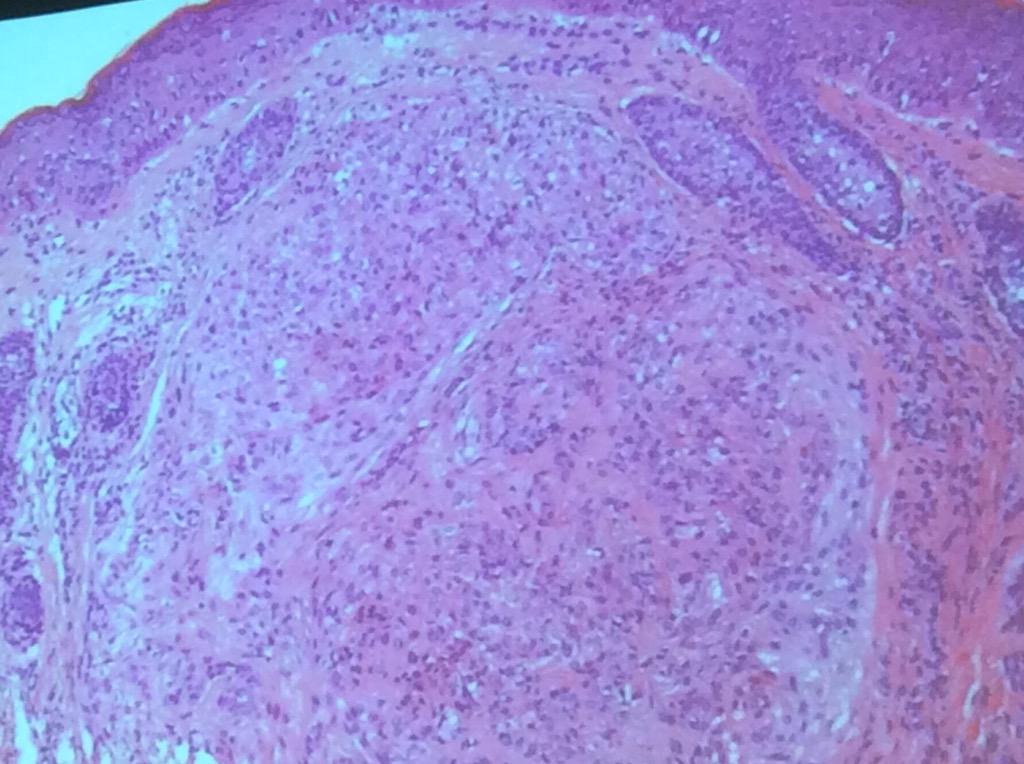

Angiomatoid fibrous histiocytoma Dr. Billings #OSAP15 always has the pseudocapsule and lymphoid aggs. @JMGardnerMD